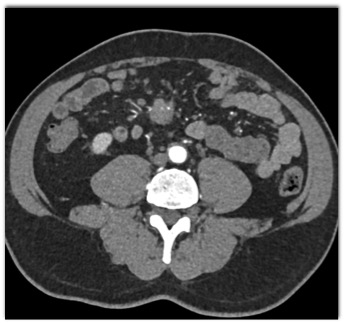

The most likely diagnosis in this case is?

multifocal hepatoma

metastatic renal cell carcinoma

carcinoid tumor

GIST tumor